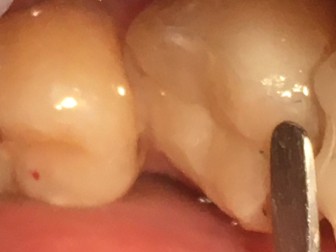

Caries avanzada, muy

cerca del tejido pulpar.

Evitando una endodoncia

con el uso de CARIESEND

El gel CARIESEND se aplica una gota y deja

actuar por dos minutos

Se aplica CARIESEND y repite el proceso hasta

lograr una cavidad limpia